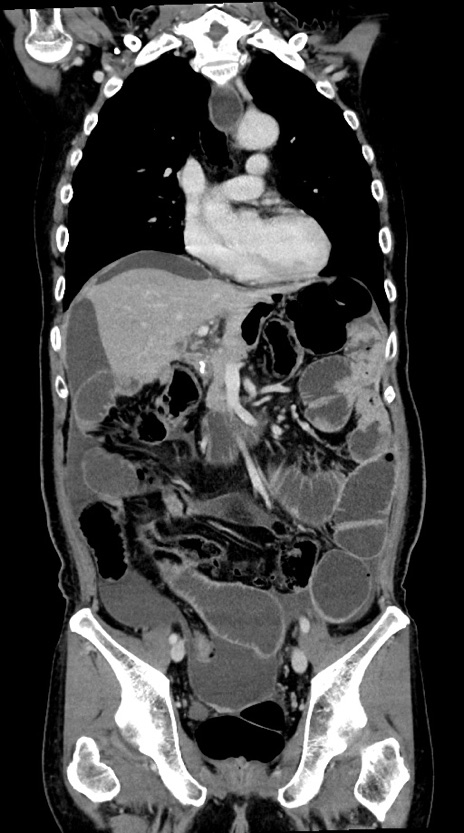

症例28(冠状断像)

【症例】60歳代男性

【主訴】嘔吐

【現病歴】胃癌にて胃全摘後。食思不振が悪化し、夜中に嘔吐することがある。

【既往歴】胃癌、胃全摘、脾摘、胆摘後

【データ】WBC 5900、CRP 10.56